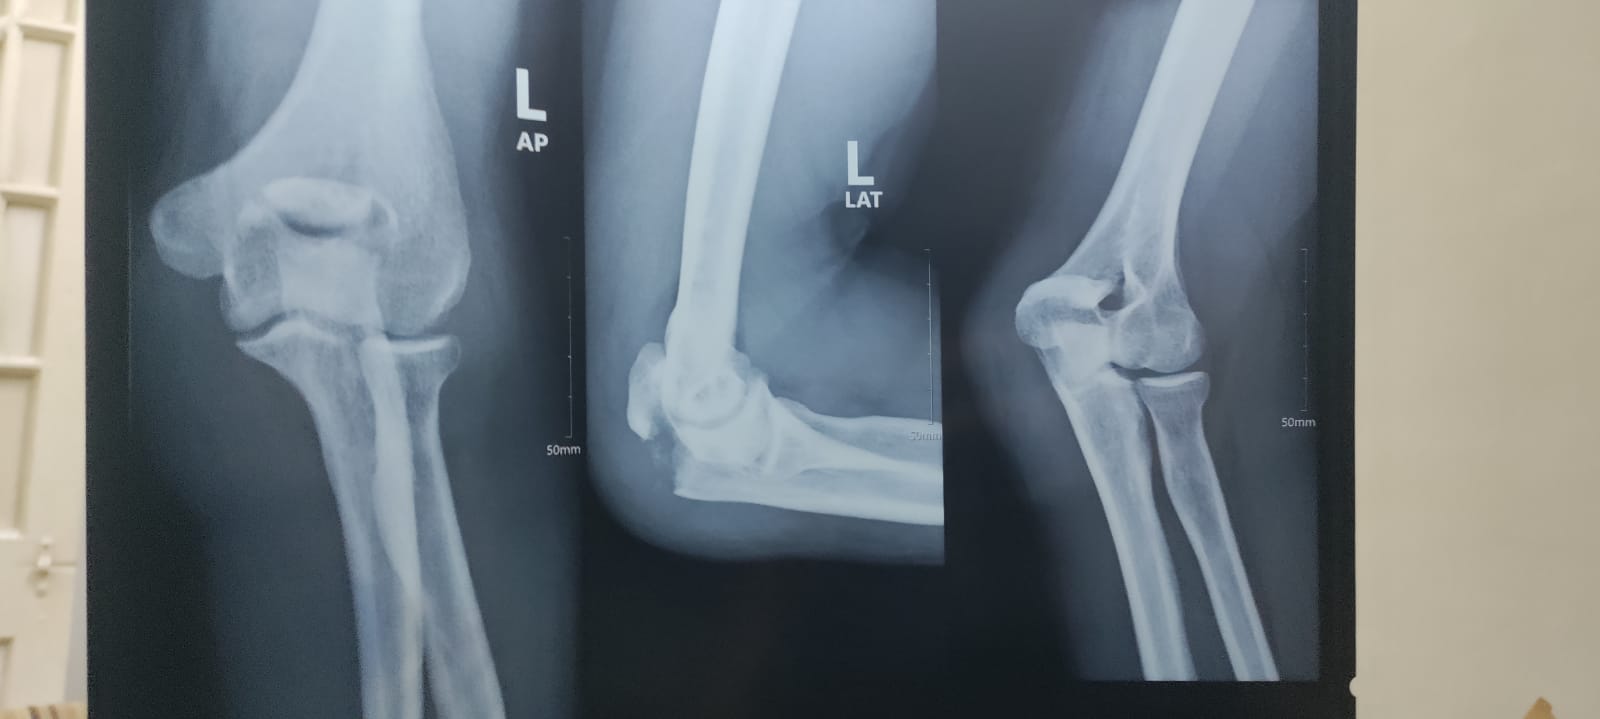

I had an accident from bike, i landed on my left elbow that lead to damage something in my elbow, can u check my x-ray and let me know whether it can heal by just using sling, or is operation needed

Looks old displaced fracture of your olecranon bone. Considering your young age, surgery is required.

Sooner the better.

Assalamu Alaikum Dear, Ideally proper history and examination should be obtained before suggesting any kind of treatment. At your age with given data, query and this kind of injury, surgery is the best treatment for optimal output. Thanks

Fracture Olecranon needs Surgery.

It's displaced znd will not heel.

Assalamualikum, 1st history and examination is needed, any wound on the fracture site? there are muscles attached to the tip of this bone that will keep the broken piece away from main bone so surgery is the best option.. where the 2 bone pieces will be brought together and fixed. without surgery bone will not heal and also the elbow joint will be restricted.

surgery should be considered.

needs fixation .